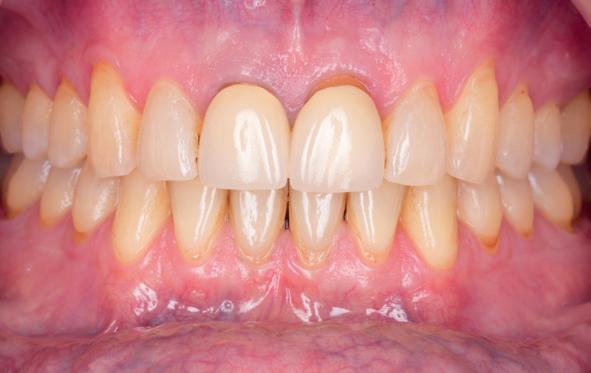

• Intra-orale scan voor studiemodellen, proefopstelling en beoordelen ruimte palatinaal

Vervaardigen essix retainer met dummies waarbij er een emergence profile van de 11 en 21 werd gevormd door eivormige dummies 4 mm in de gingiva te plaatsen

• Aanvulling zachte weefsels met de VISTA techniek en een vrij gingivatransplantaat uit het palatum links en direct dragen van de essix retainer

Na 4 weken intra-orale scan voor de etsbrug en kleurbepaling bij de technicus

• Plaatsen van de etsbrug met een composietcement

Voordat er gescand kon worden voor een etsbrug, werd een studiemodel vervaardigd om met de technicus te overleggen of er voldoende ruimte was voor 2 centrale incisieven in de mesio-distale zin en of er voldoende ruimte was in occlusie voor de vleugels van de etsbrug. Er hoeft enkel nog aan de 12 en 22 pala-

tinaal geslepen te worden als er geen 1,5 mm ruimte voor de vleugels behaald kan worden. De ruimte was op de dunste plekken 1 mm, dus een kleine preparatie in de 12 en 22 palatinaal was nodig. Omdat de kaak volledig afgevlakt was en dun was geworden, kunnen de dummies van de etsbrug enkel op de kaak “gelegd worden”, maar daarbij zijn er geen papillen en staat de cervicale rand van de dummies net voor de kaak. Een esthetisch resultaat kan daarmee niet behaald worden. Daarom is een aanvulling van de zachte weefsels in de breedte nodig, als het creëren van een emergence profile, waarbij het oogst alsof de gebitselementen uit het weefsel vertrekken.

Voor de aanvulling zachte weefsels chirurgie werd gekozen voor de VISTA techniek, hierbij worden er twee incisies partial thickness flap hoog in de mucosa gemaakt, waarna er ruimte vanuit de incisies wordt getunneld tussen de gingiva en het periost door middel van VISTA tunnel instrumenten. Uit het palatum links werd een vrij gingivatransplantaat geoogst van 15x10 mm met een dikte van 3 mm, die voor inhechten werd geëpithelialiseerd. Als het epitheel niet wordt verwijderd, kan deze graft door

de mucosa heen groeien, dat ten koste gaat van de esthetiek. In het donorgebied wordt een collageen spons ingehecht, waardoor de patiënt daar minder last van heeft. Het bindweefsel wordt door de hul-

pincisies met hechtingen naar het buccale en coronale deel getrokken en aldaar ingehecht. Met twee incisies werd ook de emergence profile gecreëerd (afbeelding 6-13). Voor een goede genezing van het

5. Beginsituatie voor behandeling

6. VISTA techniek twee hulp incisies

7. Vervaardiging tunnel met tunnelinstrumenten

8. Geoogst bindweefseltransplantaat uit palatum

9. Na de-epithelialiseren van transplantaat

10. Inhechten van een collageenspons in het donorgebied

11. Middels hechtingen het op de juiste plek trekken van het transplantaat

12. Transplantaat ingehecht

13. Occlusaal beeld verdikking van de zachte weefsels

14. Direct postoperatief plaatsen

van de essix met 2 dummy tanden

15. Twee weken post operatief

16. Creëren van een duidelijke indeuking in de mucosa voor emergence profile

17. Genezing van het palatum

18. Etsbrug frontbeeld

19. Etsbrug palatinaal